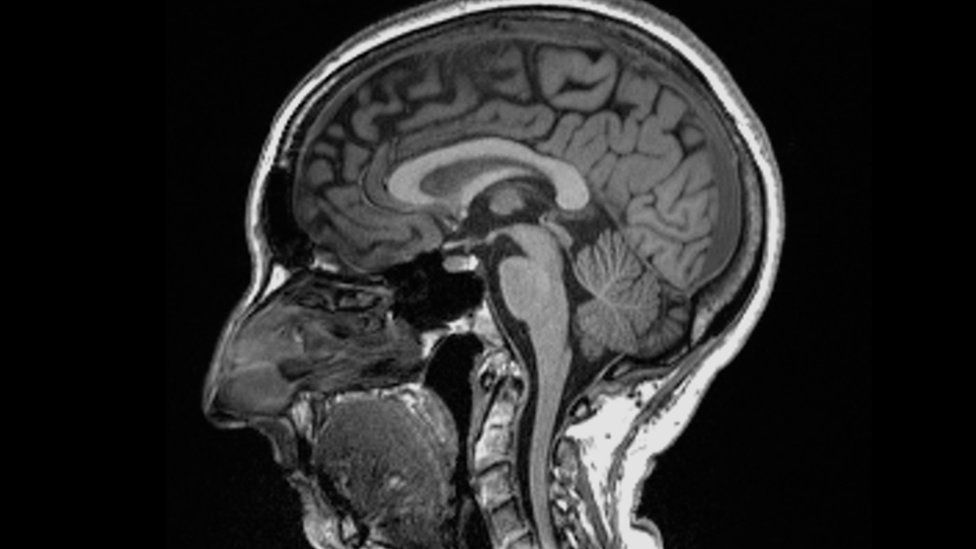

Shkencëtarët gjetën dallime të rëndësishme në skanimet MRI (imazhe me rezonancë magnetike) para dhe pas infeksionit. Edhe pas një infeksioni të lehtë, madhësia e përgjithshme e trurit ishte zvogëluar pak, me më pak lëndë gri në pjesët që lidhen me nuhatjen dhe kujtesën.

Studimi është publikuar në revistën Nature. Autori kryesor, profesor Gwenaelle Douaud nga Qendra Wellcome për Neuroimazhe Integrative, në Universitetin e Oksfordit, tha: “Ne po shikonim një infeksion në thelb të butë, kështu që për të parë se ne mund të shihnim vërtet disa ndryshime në trurin e tyre. Dallimi krahasuar me ata që nuk ishin infektuar ishte befasi”.

Madhësia e përgjithshme e trurit në pjesëmarrësit e infektuar ishte tkurrur midis 0.2 dhe 2%.

Pati humbje në lëndën gri në zonat e nuhatjes, të lidhura me nuhatjen dhe rajonet e lidhura me kujtesën. Ata që ishin shëruar së fundmi nga COVID-19 e kishin pak më të vështirë të kryenin detyra komplekse mendore. Por studiuesit nuk e dinë nëse ndryshimet janë të kthyeshme apo me të vërtetë kanë rëndësi për shëndetin dhe mirëqenien.

“Duhet të kemi parasysh se truri është vërtetë plastik, me këtë nënkuptojmë se mund të shërohet vetë, kështu që ekziston një shans shumë i mirë që me kalimin e kohës efektet e dëmshme të infeksionit të lehtësohen”, tha Prof Douaud.

Projekti UK Biobank ka ndjekur shëndetin e 500 mijë njerëzve për rreth 15 vjet dhe ka një bazë të dhënash të skanimeve të regjistruara para pandemisë, kështu që ofroi një mundësi unike për të studiuar ndikimet afatgjata shëndetësore të virusit.

Humbja më e madhe e lëndës gri ishte në zonat e nuhatjes, por është e paqartë nëse virusi sulmon drejtpërdrejt këtë rajon apo qelizat thjesht vdesin nga mungesa e përdorimit pasi njerëzit me COVID-19 humbasin shqisën e nuhatjes. Është gjithashtu e paqartë nëse të gjitha variantet e virusit e shkaktojnë këtë dëm.